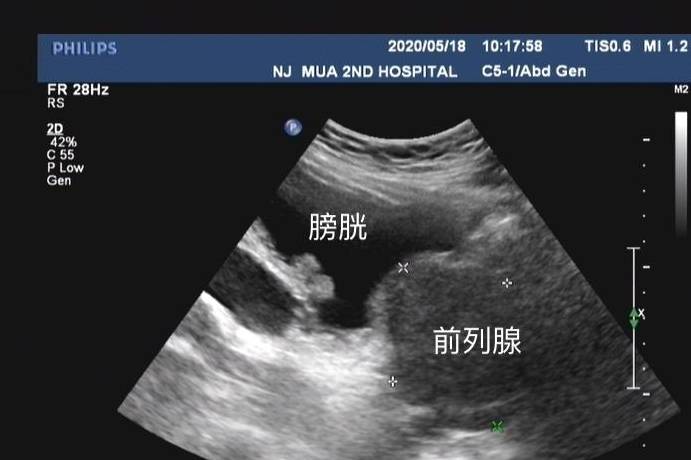

— 前列腺增生患者的动脉栓塞疗效究竟怎么样?一篇文章带你简单认识 —